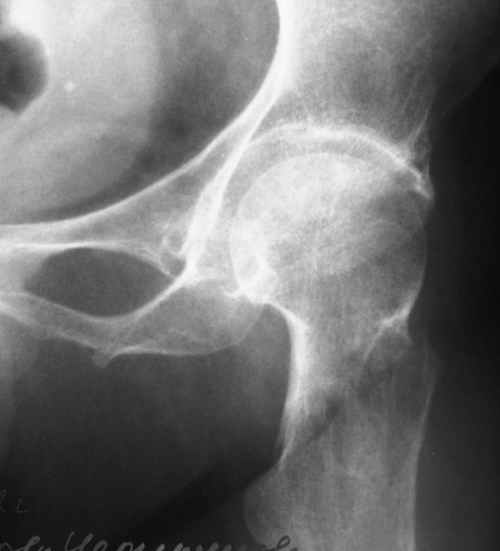

Приветствуем из Сергиева Посада. Нужен совет. Поступила в отделение больная с переломом шейки парализованной укороченной н.конечности. ШДУ почти 180°. На деротационной шине. Чем лучше фиксировать? Винтами? А штифт с диафизарной накладкой и под каким углом проводить? Или эндопротезирование лучше? А как быть с укорочением до 3 см, изменены все суставы, конечность только опорная. Снимки первоначальные, соответствующего качества.Сергиево-Посадская РБ

Насчет ШДУ 180 градусов - снимок, скорее всего, сделан в наружной ротации.

Представляется, что обычный остеосинтез спонгиозыми винтами тут вполне приемлем. Если доступны динамические бедренные винты и клинковые пластины с углами больше 130 градусов, реконструкционные или проксимальные гвозди, то и их вполне можно применить, только рентгенологически дообследовать, чтобы неожиданностей не было на операции. Я бы не стал сейчас планировать реконструкцию конечности этак вот попутно, из-за этой "счастливой случайности". Пациент, надо полагать, был как-то адаптирован к жизни с имеющейся длиной и формой конечности. Так что вернуть бы его в привычное состояние.